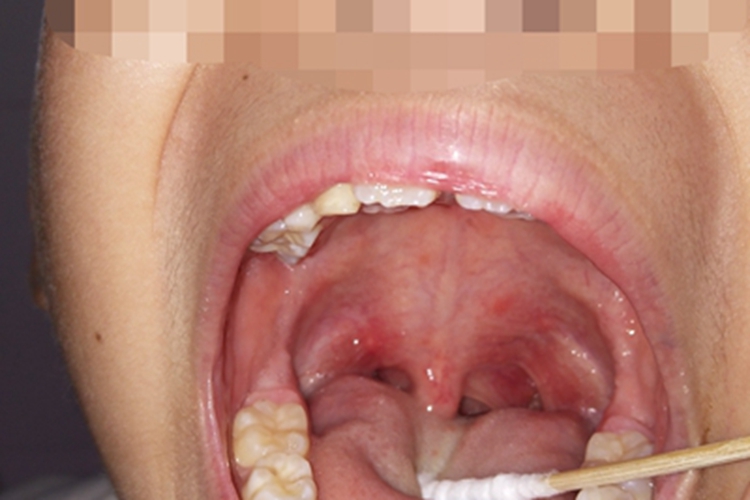

咽峡炎发生后,部分患者咽峡可出现红肿的表现,同时伴有发热、咽痛等症状。

咽峡炎多起病急骤,疾病发生后,部分患者咽峡可出现红肿的表现,同时伴有发热、咽痛、咽干、异物感等症状,有些患者可在咽部出现白色疱疹,需尽早就医治疗。